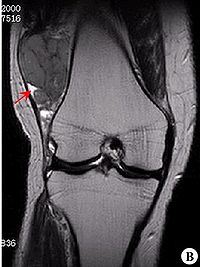

滑膜肉瘤起源于滑膜、滑囊和腱鞘,是发生频率较高的一种软组织肉瘤以四肢最好发,尤其是膝关节,外与关节无关的部位如头颈部、腹壁、后腹膜也可发生。 全身凡有关节滑膜、滑囊、腱鞘均可受累,一般原发于关节囊外,后穿入关节囊。可发于任何年龄,但以20~40岁见。男多于女,病理长短不等,以1年左右多见。

滑膜肉瘤是发生频率较高的一种软组织肉瘤,好发于15-40岁,四肢的大关节附近,特别是膝关节附近好发,另外与关节无关的部位如头颈部、腹壁、后腹膜也可发生。本病的基本X线表现有三点:软组织肿块,局部骨皮质破坏,肿瘤的钙化和骨化。此病好发于关节附近,呈分叶结节状,密度增高,边界清楚的软组织肿块。其内可见骨化影,呈条状或块状轮廓清楚的高密度影,部分骨化影中可见骨小梁结构,少数病例为骨化性肿块。应与骨旁骨肉瘤、骨化性肌炎、骨肉瘤等鉴别。

X线表现

(1)软组织肿块。临床所能触及的肿块并不都在X线上显示出来。有的表现局部软组织肿胀,有的出现软组织肿块。一般肿块密度较邻近软组织稍高,大小不等,小的只有豌豆大,大者可巨大,有跨越关节生长的特点。

(2)软组织肿块钙化。软组织肿块内可见到不定形、不规则钙化影,占30%。钙化的原因可能与出血、感染、坏死及软骨钙化等有关,且钙化的多少与肿瘤恶性度有关,钙化越少,恶性度越高。

(3)骨骼改变。会出现不同程度骨质压迫、缺损或溶骨性破坏。譬如骨质疏松,骨萎缩畸形,囊性骨缺损,骨质糜烂,溶骨性破坏,关节改变。骨质轻度疏松为早期表现,以后压迫性骨萎缩、变细或囊性缺损,进一步发展出现骨质破坏。骨破坏大多呈不规则状,也可呈囊状,跨关节者可侵及多骨。本病一般关节无改变,但偶尔可有侵入关节,使间隙增宽或出现软组织肿块,也可出现关节积液,易误诊为关节疾患。

(4)骨膜反应。可出现平行、花边状或针状骨膜反应,有些虽未见到明确骨膜反应,但邻近骨皮质可见到刺状突起。可能出现Codman三角。